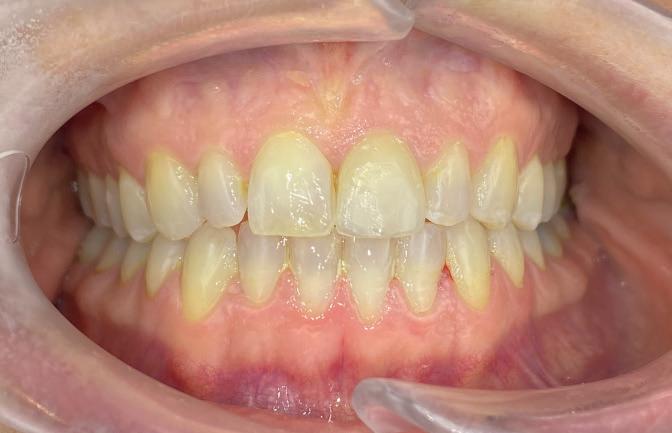

Timothy Zoltie is Head of the Medical & Dental Illustration Department, based within the School of Dentistry at the University of Leeds, in a collaborative role with Leeds Teaching Hospitals NHS Trust. He is an award-winning professional photographer and videographer, in the speciality area of medicine and dentistry. A Fellow of the Institute of Medical Illustrators, as well as a Fellow of the Royal Photographic Society, Timothy Zoltie also works as Editor in Chief of the Journal of Visual Communication in Medicine.

The School of Dentistry at the University of Leeds stands as a preeminent hub for dental education and research, distinguished by its expert faculty and state-of-the-art training facilities. Renowned as a leading centre for dental study, the school is committed to shaping the future of dentistry by nurturing the skills of the next generation of dental professionals. A unique element of the institution is that it has a dedicated Dental Photography Department, one of only a few in the world. The dental photography department at the University of Leeds has been delivering high-quality dental photography services for over 60 years, and currently photographs over 8,000 patients per year.

In reviewing the market for camera systems to use for dental and clinical photography, Timothy was looking for a compact solution that would capture the highest-quality images, while offering versatility to shoot stills and video.

solution and results

After reviewing the various options, Timothy chose the Sony Alpha a7R V Mirrorless camera system. In capturing stills and video, the camera provides the versatility Timothy was looking for in his hybrid role, where he not only photographs clinical conditions but also undertakes clinical videography. The seamless interchangeability of lenses for video and stills on a single system significantly enhances workflow efficiency. The compact form factor of Sony cameras improves manoeuvrability and user comfort, which is particularly advantageous for repetitive tasks such as intra-oral photography. Manual focusing for Timothy is crucial in dental

photography for maintaining consistent working distances and is facilitated by the Sony 90mm Macro G OSS lens. It is the only mirrorless lens in its focal range equipped with lens distance scales and ratios on the barrel.

“The Sony FE 90mm Macro G is one of the sharpest macro lenses I have used, Timothy explains. “Clarity is imperative when undertaking clinical photography and paired with a high-resolution camera such as the Sony Alpha 1 or Sony Alpha a7R V, it allows exceptional documentation of clinical detail.”

When Timothy is shooting in clinical conditions, where stopped-down apertures of f/22 are used for increased depth of field, effective lighting is crucial. Flash is the key source of illumination and the Godox MF-R76S+ Ring Flash developed jointly with Sony Europe is used with the Sony Alpha camera. This dedicated dental kit is easy to set up and delivers the required picture quality in combination. The optimised dental kit compatibility for Sony Alpha cameras provide highly accurate E-TTL functionality that produces the correct exposure on every shot, regardless of camera-tosubject distance.

Another camera feature Timothy uses is custom modes. This enables standardised settings for specific tasks, streamlining workflows and minimising errors. For example, custom mode 1 can be assigned for intraoral photography, and custom mode 2 can be designated

t imothy recommends that other dental professionals considering using sony alpha cameras should test the kits that fit their practice, explore the system’s versatility, and invest in dental photography training.

He said: “take time to understand the camera’s features and functionalities to unlock the full potential of the camera, such as how to calibrate and set up custom modes, and how to switch between them. Once calibrated, the sony system paired with the dedicated Godox MF-R76s+ for sony alpha cameras is by far one of the easiest camera set ups for dental photography and can be used by any of the dental team.”

for videography, with all the associated settings for each mode saved.

The adoption of Sony Alpha cameras at the University of Leeds has significantly elevated the quality and efficiency of dental photography and videography. Timothy Zoltie’s experience highlights the importance of a versatile and user-friendly camera system in the specialised field of dental imaging.

Timothy said: “Choosing a hybrid system has proven very advantageous, seamlessly facilitating the interchangeability of lenses for

both video and stills. This versatility enables me to effortlessly transition between filming surgical procedures and undertaking commercial healthcare photography commissions for marketing agencies or NHS institutions.

“The Sony Alpha cameras’ hybrid functionality, complemented by features such as manual focusing and custom modes, makes them ideally suited to dental photography and they have become indispensable assets for documenting clinical procedures and conditions at the School of Dentistry.” n www.masteringdentalphotography.com